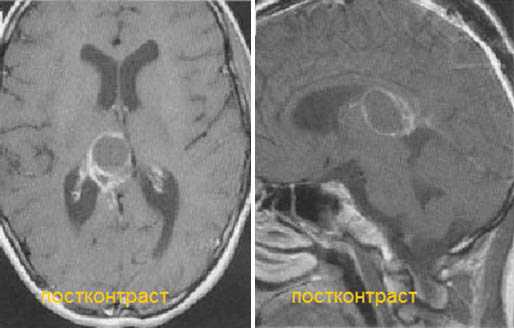

Злокачественная смешанная герминативноклеточная опухоль. В боковых желудочках и пинеальной области определяются множественные опухолевые узлы с выраженным перитуморальным отеком. Внутрижелудочковые образования с признаками кровоизлияний. При в/в контрастировании определяется выраженное контрастирование узлов. Дополнительно визуализируется метастазирование по эпендиме боковых и IV желудочков мозга.

Киста эпифиза. Компрессия четверохолмной пластинки и частичное сдавление водопровода мозга.